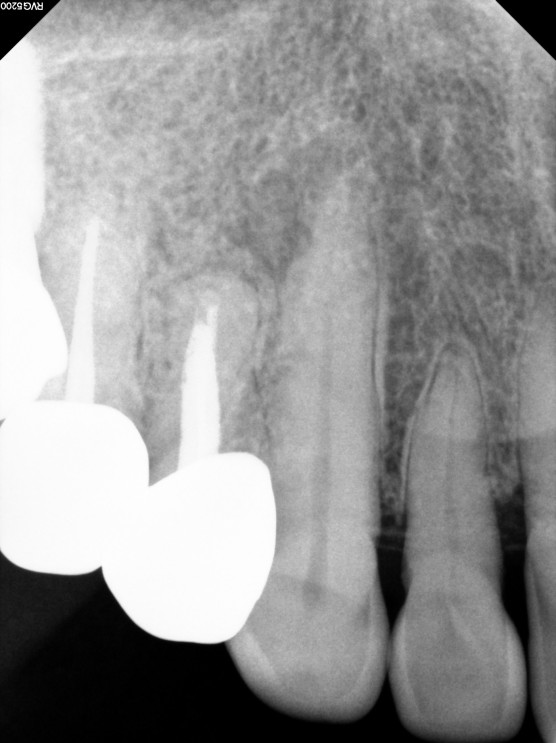

마무리 후 x-ray 촬영